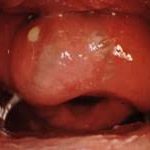

Kanama sıklıkla nereden kaynaklanır?

📍 En sık kaynak:

Kiesselbach pleksusu

(burnun ön-alt septum bölgesi)

Bu bölge:

-

Yüzeyel

Çok damarlı

Kurumaya ve travmaya çok hassas